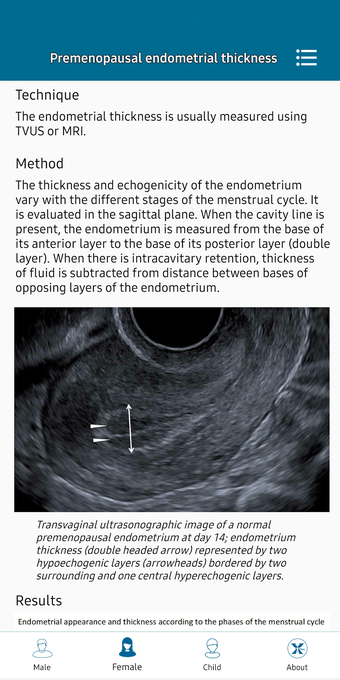

This helpful app is intended for all those who practice medical imaging and for the radiologists who use the application in their work. It is an atlas of the main measurements in radiology and their normal values, divided into six subspecialties: osteoarticular, cervical region, thorax, cardiovascular, abdomen, and pelvis.